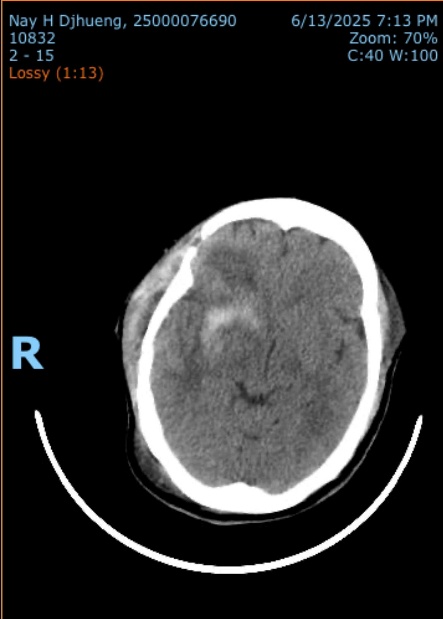

2.2. Xử lý các trường hợp đột quỵ não cấp: Phối hợp với các khoa liên quan để điều trị toàn diện. Phẫu thuật lấy máu tụ hoặc mở sọ giải áp khi có chỉ định các ca xuất huyết não, nhồi máu não,…

Phẫu thuật lấy máu tụ nội sọ